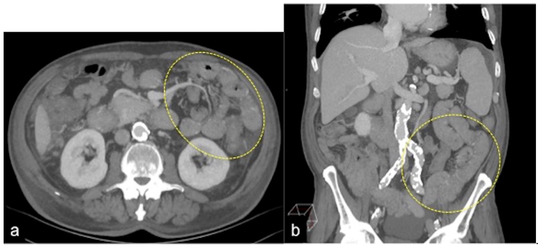

| Meckel’s Diverticulum (Figure 30) | Asymptomatic or, rarely, massive gastrointestinal bleeding. | A diverticulum with fluid or air content originating from the antimesenteric side of the distal ileum. |

| Jejunal-Ileal Diverticulum | Asymptomatic or, rarely, massive gastrointestinal bleeding. | Similar to Meckel’s diverticulum. |